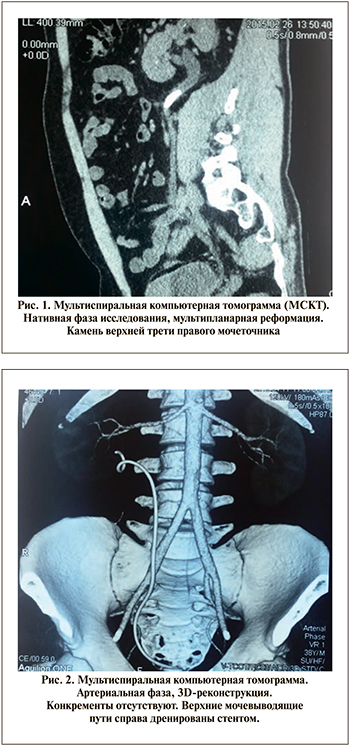

Для демонстрации возможностей ЦТ в растворении МК мочеточников приводим следующее клиническое наблюдение:

Пациент И. 38 лет, и/б No 10957/2015. Клинический диагноз: МКБ. Камень верхней трети правого мочеточника. Камни правой почки. Хронический пиелонефрит.

По данным мультиспиральной компьютерной томографии (МСКТ) (рис. 1) выявлен камень верхней трети правого мочеточника 6x6,5x23 мм плотностью +504 HU, микролиты средней и верхней групп чашечек правой почки до 2 мм.

С учетом высокого риска развития острого обструктивного пиелонефрита верхние мочевыводящие пути справа дренированы стентом. Пациенту проведен курс антибактериальной противовоспалительной терапии. После стабилизации состояния, подтверждения стойко кислой pH мочи на протяжении 43 сут. проводилась терапия цитратными препаратами с поддержанием pH мочи на уровне 6,8–7,1.

При контрольной МСКТ (рис. 2) конкременты в верхних мочевыводящих путях справа не выявлены. Мочеточниковый стент удален.